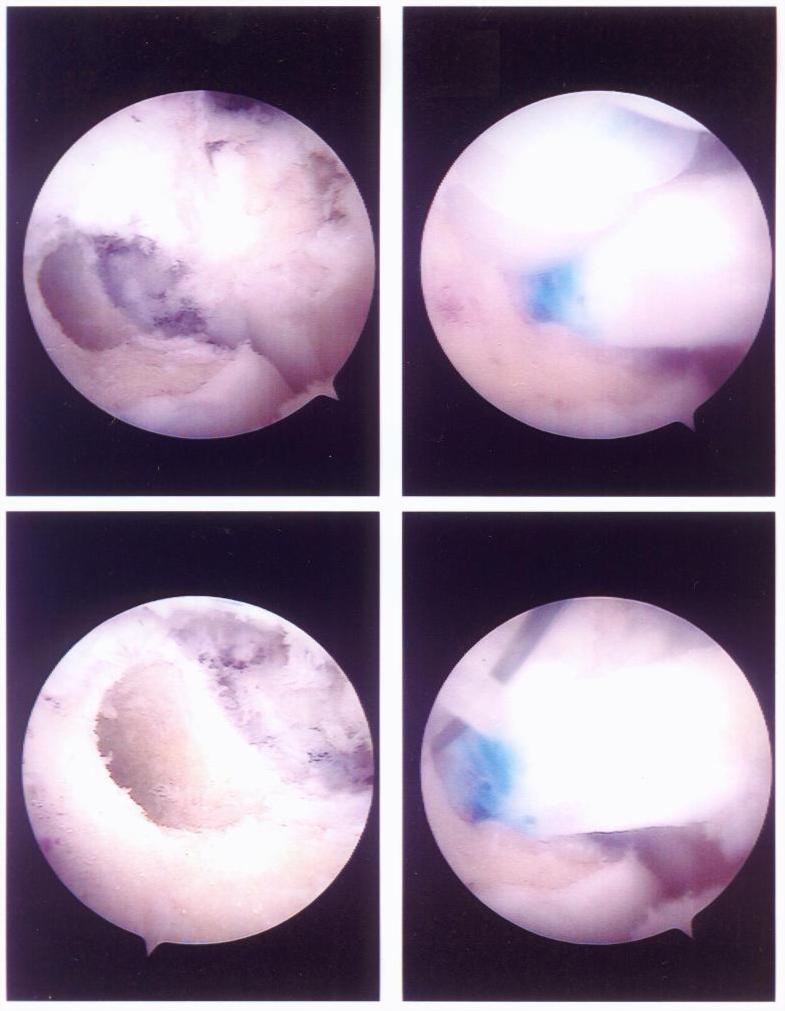

Here are four pictures showing the holes and donor tendon. The blue marks on the allograft are to show the surgeon how deep he was to place tendon into the bone.

This show the holes drilled in the bone inside David's knee

David's Page You can see the tendon (now a ligament) in place.